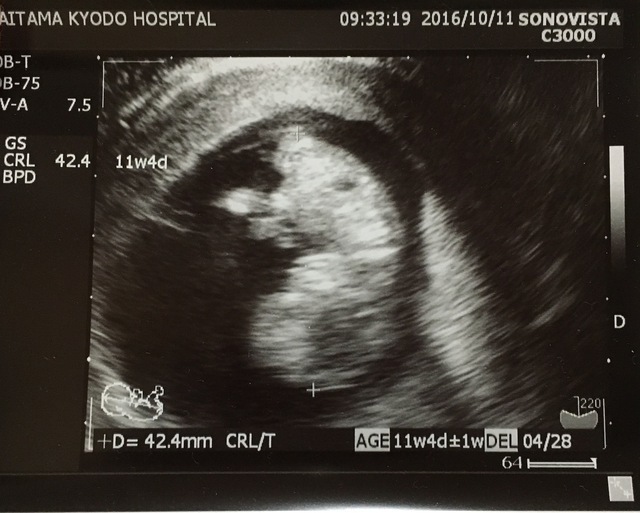

11週4日(11w4d・男の子)|ななななななな さん(32歳)

エコー写真撮影時のエピソード:

不妊外来に通いようやく妊娠できたので、主人もとても喜んでおり、健診でエコー写真をもらってくるのをとても楽しみにしていました。

人の形らしくなり、手をバタバタしているのが見れた日なので、とても感動した日です。